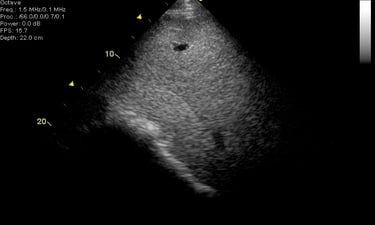

In sommige gevallen is aanvullend een echografie van de longen aangewezen. Dit wordt steeds per situatie beoordeeld en met u besproken.

Een bloedonderzoek toont aan dat de leverwaarden niet optimaal zijn. Een gerichte anamnese en en inspectie van de omgeving (toxische stoffen, voeding, aanwezigheid andere dieren....) is zeer belangrijk bij de aanpak van een leverprobleem. een echografie van de lever kan soms de oorzaak van het leverprobleem aantonen (abces, verstopte galgangen, steentjes of gruis, gezwollen ontstoken lever, tumor). Lees het artikel over leverproblemen bij paarden.....

Paarden kunnen uitzonderlijk een nierprobleem hebben. Echografie van de nieren, al dan niet gecombineerd met een endoscopie van de urinewegen kan een meerwaarde zijn om de oorzaak van het probleem aan te pakken.